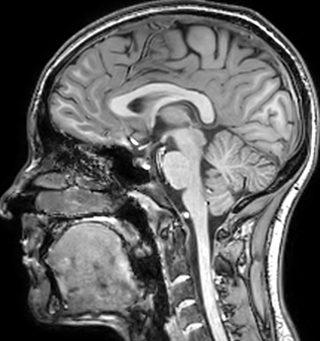

Multiple sclerosis or MS is a neurodegenerative disease that is characterized by myelin degradation, resulting in cognitive and motor deficits. According to Dr. Shannon Kolind, MR imaging for diagnosis and monitoring of MS is moving to higher field strength and using more 3D sequences, as reflected in the CMSC guidelines [1-3].

“In addition to traditional imaging like FLAIR for lesion identification, we see a real push towards techniques that weren’t normally required for MS, including good highresolution 3D T1 weighted images to do volumetrics. We’ve also started looking at spinal cord imaging again, since techniques have improved in terms of acquisition and analysis. Another important technique is susceptibility weighted imaging (SWI), particularly if we are looking for central veins in lesions, which is extremely helpful for diagnosis.”